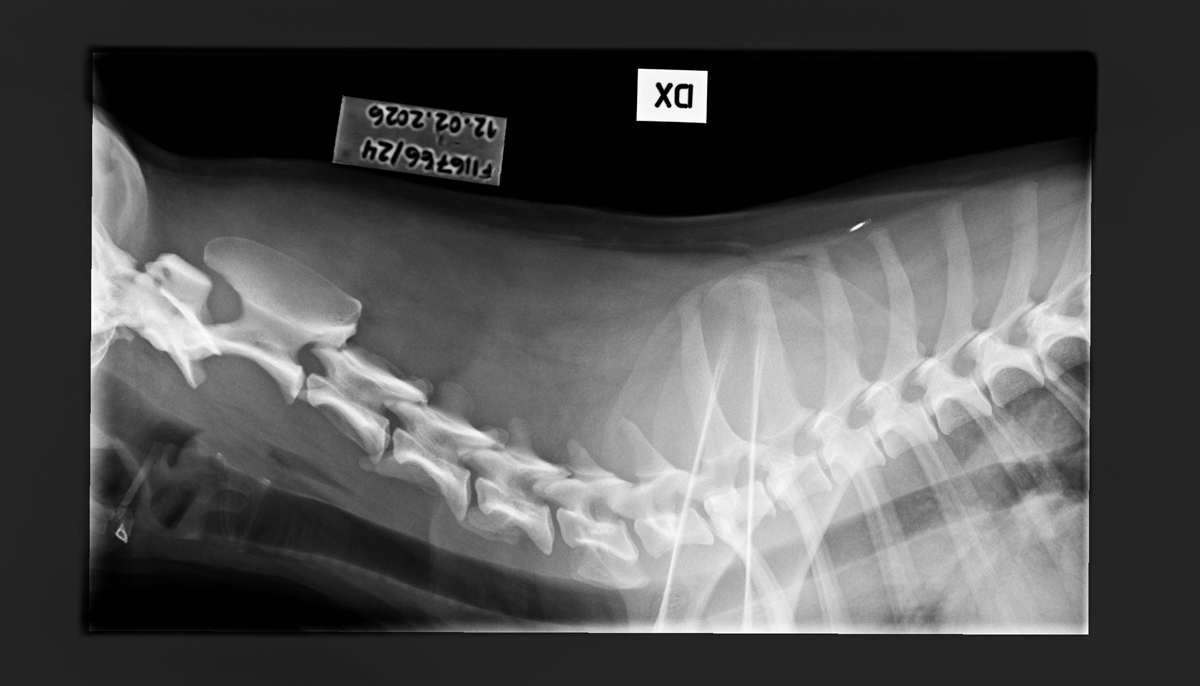

- Finnish Kennel Club's elbow x-ray report Dec '25: Signs suggestive of medial coronoid disease; further information about the condition of the joints can be obtained, if necessary, by computed tomography (CT) examination

- Finnish Kennel Club's elbow CT report Feb '26: A small amount of new bone formation around the medial coronoid process of the left elbow

- Free of lumbosacral transitional vertebrae (LTV0)

- Free of spondylosis (SP0)

- Free of vertebral anomalies (VA0)

- Spine x-rays: 1, 2 ja 3